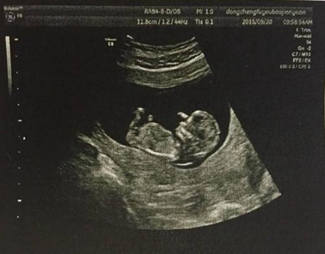

1.3.7 其他成像方式

- 应用场景:深度成像(3D 摄像头)、超声成像(医学 B 超)、偏振成像(玻璃反光去除);